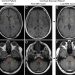

- Отложение гадолиния в головном мозге подтверждено масс-спектрометрией (повышение интенсивности сигнала в тканях мозга на МРТ).

- Данные исследований по стабильности in vitro и доклинические исследования свидетельствуют, что линейные гадолиниевые агенты высвобождают гадолиний из линейных молекул в большей степени, чем макроциклические агенты.